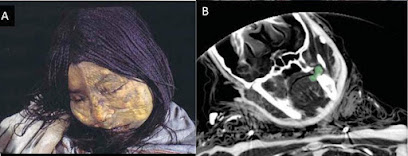

Uno de los hallazgos más

conmovedores fue el de “La Doncella”, una joven de entre 13 y 15 años encontrada en

la cima del volcán

Llullaillaco, a 6.739 metros sobre el nivel del mar. Fue descubierta en

1999 por el arqueólogo Johan Reinhard y su equipo, quienes no daban crédito a

lo que veían: «Parecía dormida. Su rostro sereno, su piel intacta. Una

niña congelada en el tiempo, con trenzas perfectas y mejillas sonrosadas»,

relató Reinhard.

| Los análisis demuestran que "La Doncella" consumió grandes cantidades de coca durante su último año de vida, mientras que solo consumió alcohol durante sus últimas semanas. Foto de Johan Reinhard. |

La Doncella, junto a dos niños

más (La Niña del Rayo y El Niño), estaba en posición fetal, rodeada de

ofrendas: estatuillas de oro, tejidos finos, vasijas con alimentos. Las

condiciones extremas congelaron sus cuerpos, conservando tejidos blandos,

cabello, uñas e incluso su expresión facial.